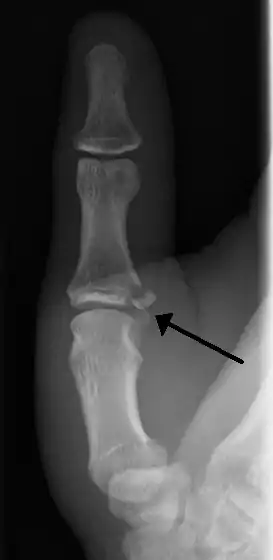

| Avulsion fractures of the ulnar base of the proximal phalanx of the thumb ( Gamekeeper's fracture ) | |

When approaching this type of injury, the physician must first determine whether there is an incomplete rupture (or sprain) of the UCL, or a complete rupture. If the UCL is completely disrupted, the physician must then determine whether there is interposition of the adductor aponeurosis (Stener lesion), or simply a complete rupture of the UCL with anatomic or near-anatomic position. Radiographs are helpful in determining the possible presence of an avulsion fracture of the proximal phalanx insertion site of the ulnar collateral ligament. Stress examination, or one done under fluoroscopic guidance, can help determine the integrity of the ligament.